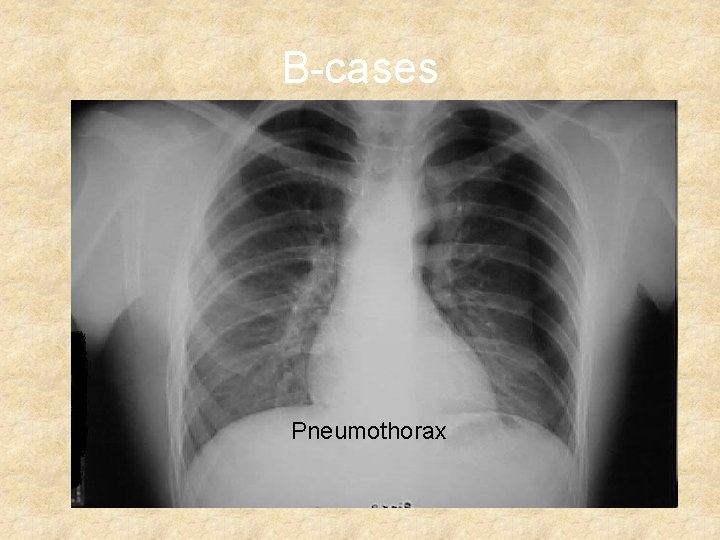

Giv ilt B-Breathing • Observationer: • Resp-frekvens, brystkassens bevægelse, anstrengt resp, St P, Sa. O 2, CO 2 i in og exp-luft, hudfarve, subcutant emphysem, RTG-Thorax. • • Problemer: Pneumothorax Trykpneumothorax Hemothorax Kombination af ovenstående Lungekontusion Flail chest

B-cases Pneumothorax